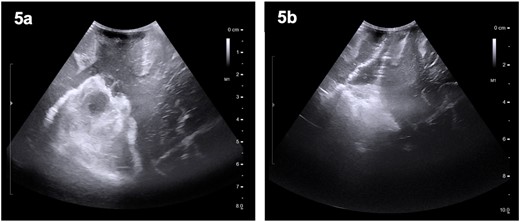

The patient was started on oral dexamethasone, resulting in the improvement of his headaches. The differential diagnosis based on imaging findings included an atypical meningioma, central neurocytoma, choroid plexus papilloma or carcinoma, ependymoma or an oligodendroglioma. He underwent a right parietal craniotomy with gross total resection of the lesion. Intraoperatively, use of the Vycor™ ViewSite Brain Access System (VBAS) was utilized, which allowed for optimized surgical site access, and reduced the risk of brain retractor injury to surrounding structures, namely the precentral gyrus. This was combined with intraoperative ultrasound (Fig. 3), which provided real time imaging and guided the extent of the resection. In addition, neuromonitoring and neuronavigation (Fig. 2) were incorporated to further reduce the risk of damage to surrounding structures. As part of the neuromonitoring, motor evoked potentials (MEPs) were performed to identify the precentral gyrus prior to insertion of the VBAS (Fig. 4), ensuring that any resection occurred posterior to the motor strip. During surgery, it was noted that the lesion was haemorrhagic and easily friable, with evidence of a previous recent haemorrhage.

Preoperative (5a) ultrasound images depicting a heterogenous mass with hyperechoic and hypoechoic regions. Post-operatively (5b), a hyperechoic region is noted; however, no distinct lesion is identified.